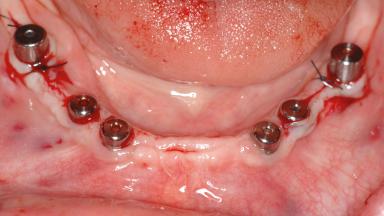

A 47-year-old woman who had suffered from aggressive periodontitis requiring a number of periodontal interventions over more than 10 years was referred by her general dental practitioner and periodontologist for bone augmentation and implant therapy. Her failing dentition had already been scheduled for extraction. The patient expressed a desire for implant-supported fixed restorations and esthetic improvement of her lower face. She had agreed to consult with a maxillofacial surgeon after the referring dentist had suggested bone augmentation. An initial examination by the maxillofacial surgeon revealed mobility of all residual teeth in a patient who was very unhappy with the function of her removable partial dentures. Due to periodontally migrated flaring teeth and loss of occlusal support, the vertical dimension of occlusion was dramatically reduced. The patient was displeased with her lower face because of deepened nasolabial, commissural, and supramental folds.

# of Implants 14

Bone Augmentation Horizontal|Sinus Floor Elevation|Staged|Vertical